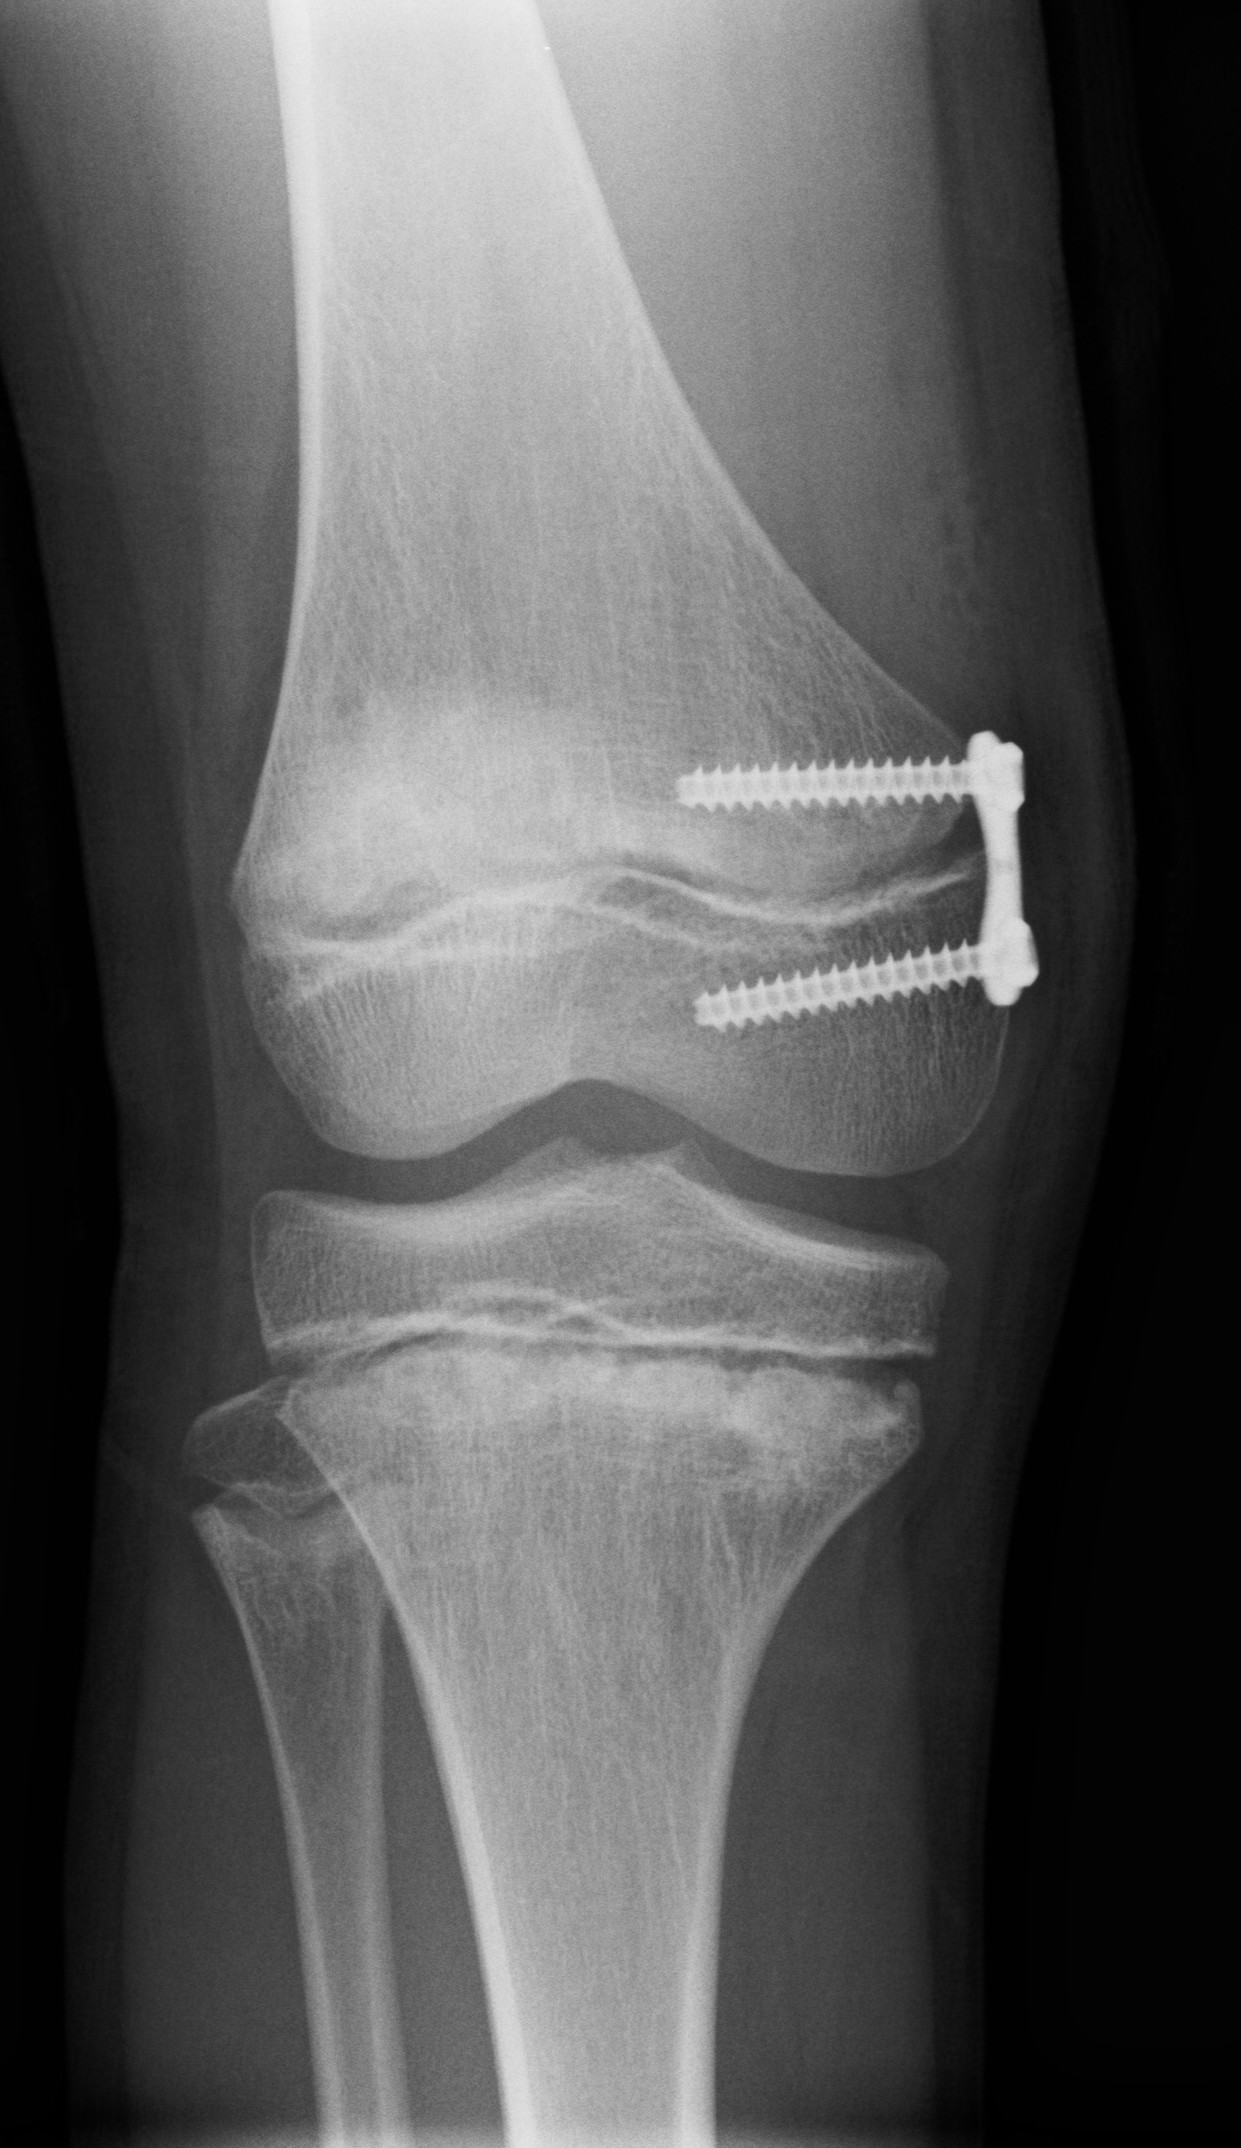

Läkaren bedömer om det finns behov av uppföljning eller behandling. Kirurgisk behandling är sällan aktuellt. Den vanligaste operationsmetoden syftar till att påverka de nedre extremiteternas position genom att utnyttja den återstående tillväxten. Under narkos placeras en platta vid tillväxtlinjen för att blockera tillväxten från plattans kant och korrigera felställningen. Plattan kan avlägsnas vid behov när korrigeringen är klar.